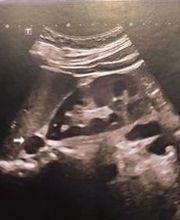

Il dr. Rina si è specializzato in Radiologia-Diagnostica per Immagini. Attualmente nello studio sono in uso due ecografi: GE E TOSHIBA-CANON APLIO I800, che permettono di effettuare, tra le altre applicazioni, attraverso la Stream Elastosonografia e la SHEAR-WAVE Elastosonografia in KPA (Kilopascal), lo studio del fegato, della tiroide, delle ghiandole salivari, dei testicoli, dei linfonodi e dei noduli sottocutanei. Lo studio del dottor Rina è sito a Marina di Nova Siri(Matera)in via Magna Grecia 57 ed è contattabile al numero telefonico 3396354005 e 0835877339.